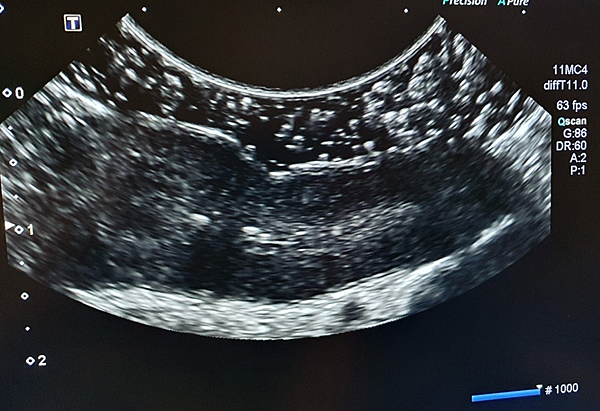

接著我們進行腹腔超音波,在掃描小腸的時候,我發現有某段小腸異常的增厚,而且分層也消失(正常小腸會有4層:黏膜層、黏膜下層、肌肉層、漿膜層,這在超音波正常都看的到);空腸淋巴結特別的腫大。

▷ 超音波下失去分層且增厚的小腸。